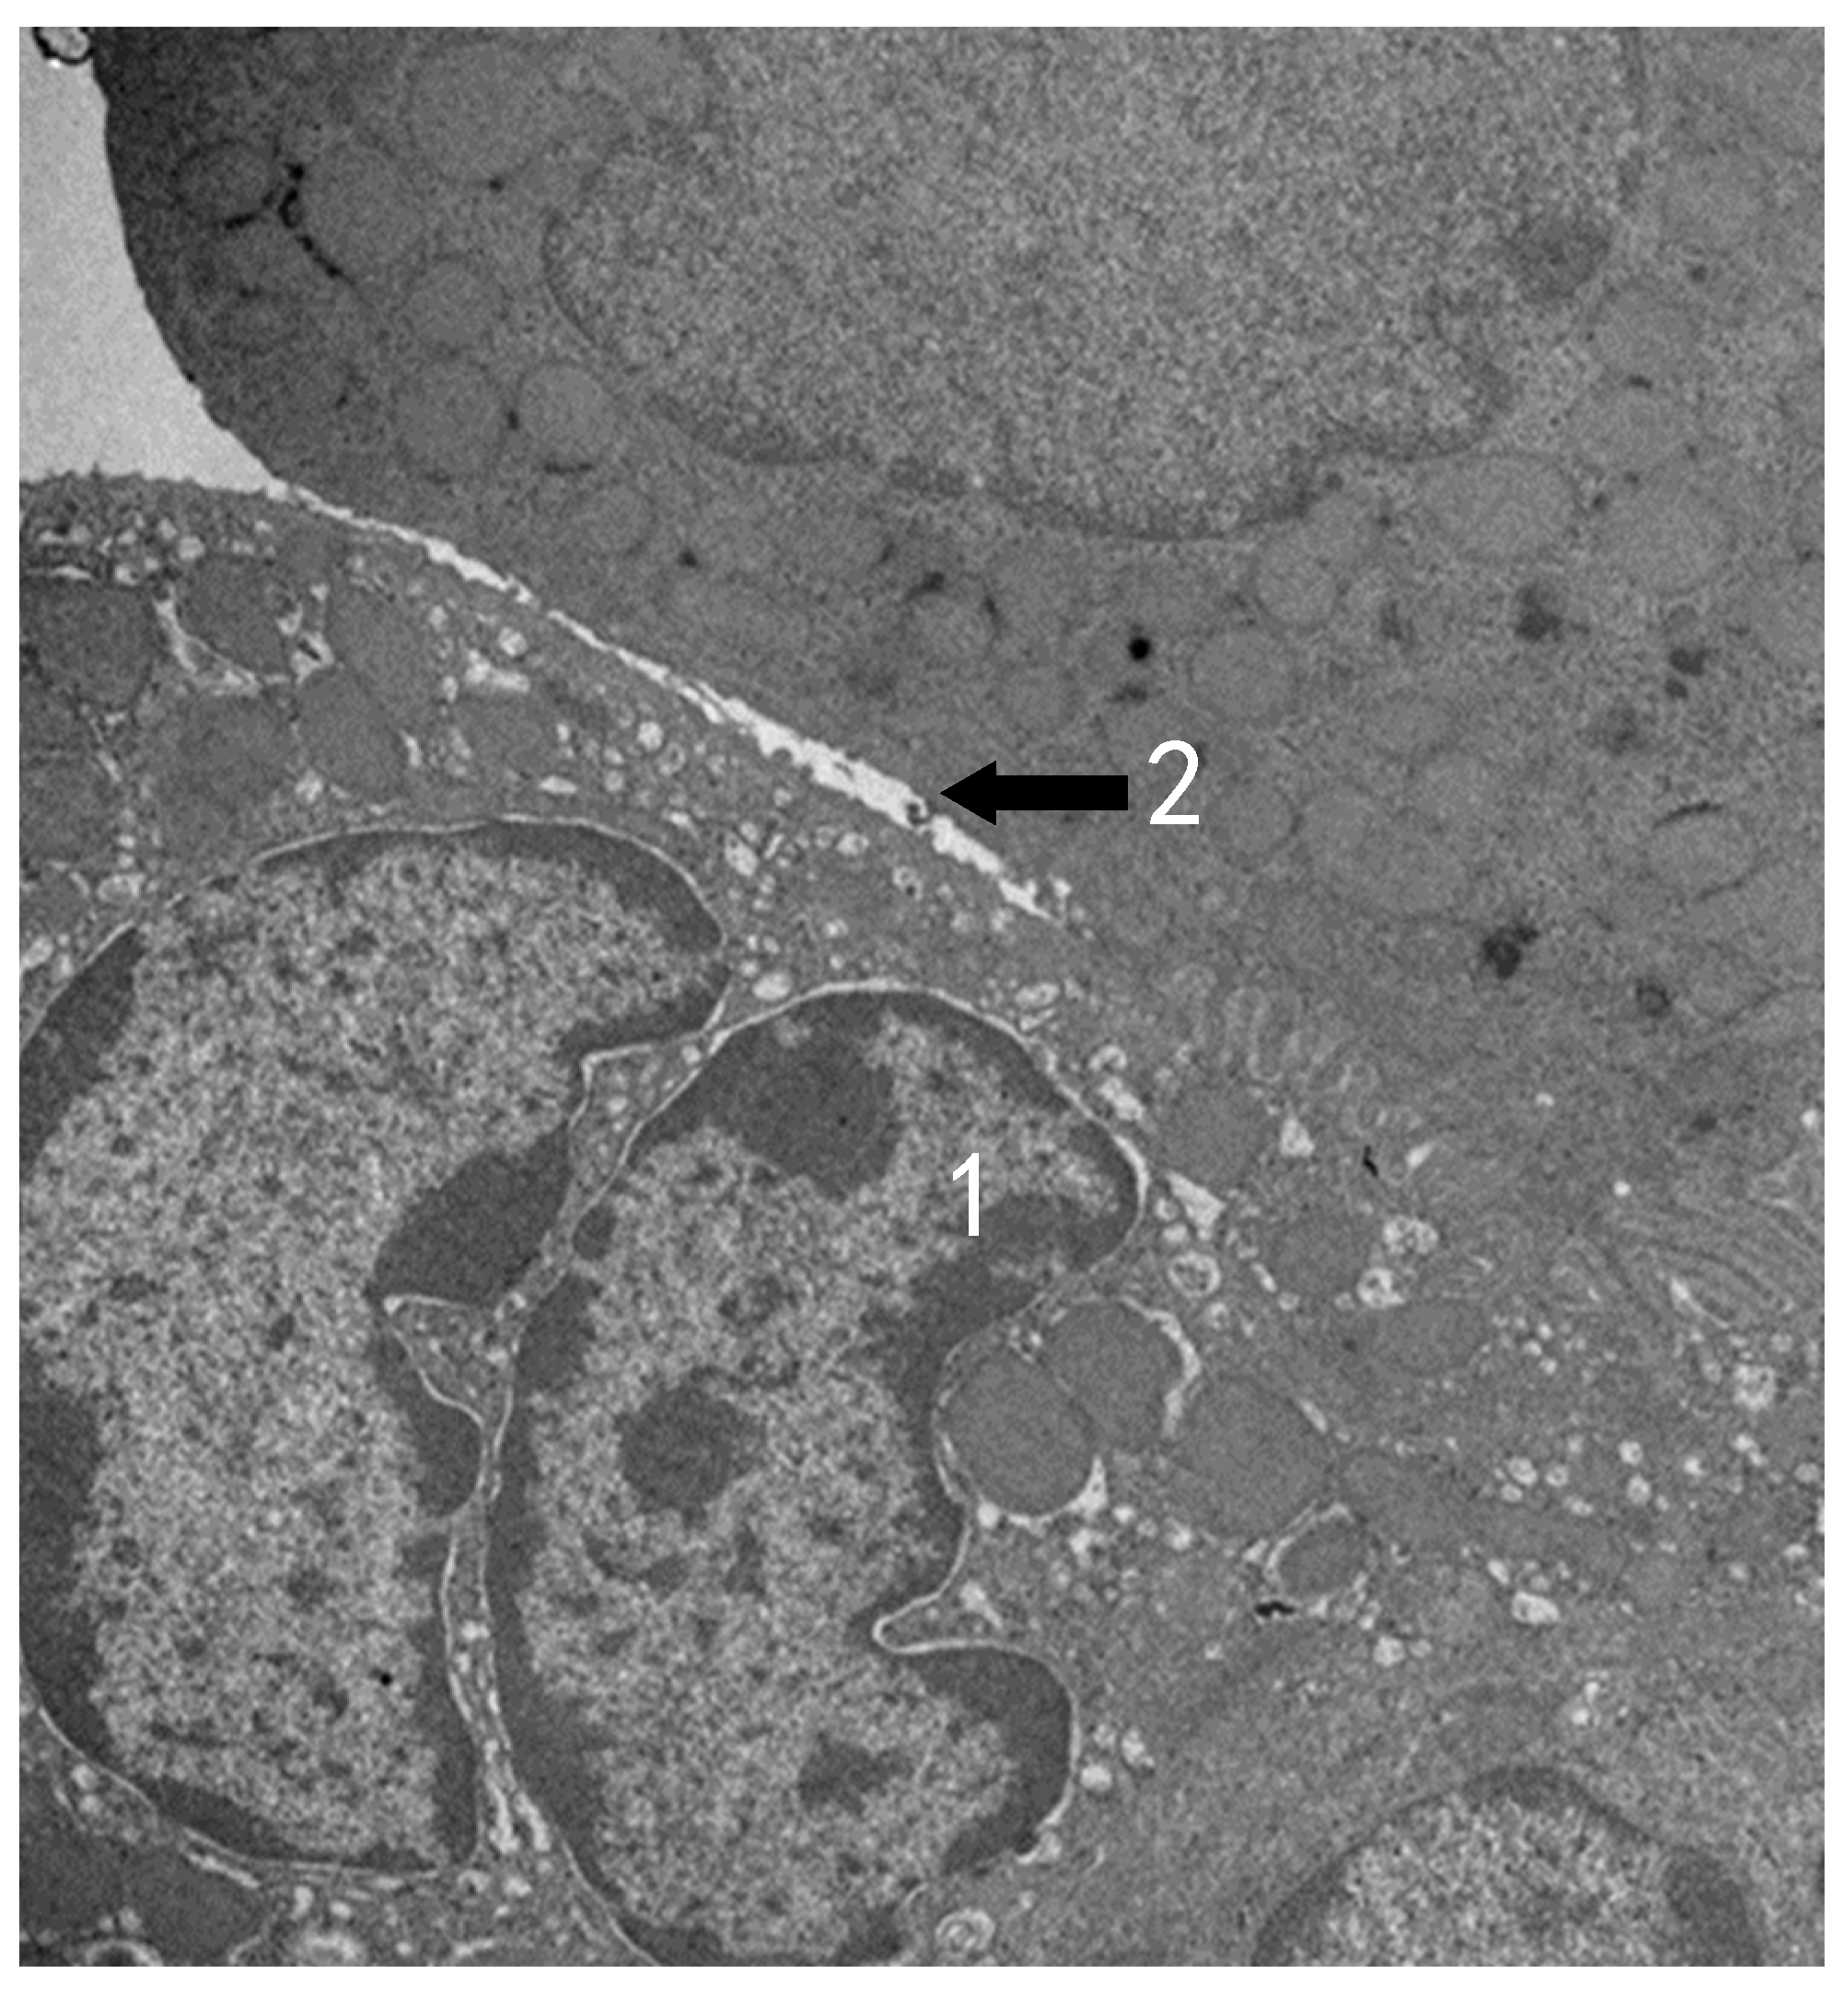

3.2. TEM Observation